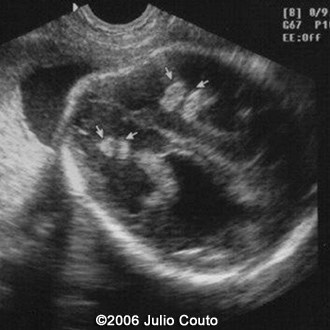

This a second-trimester-fetus with toxoplasmosis infection.

Note the dilatation of the lateral ventricles and the mild ascites